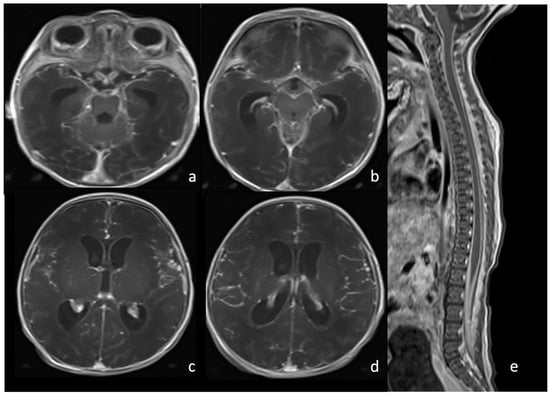

7.1. Group B Streptococcus

7.2. Listeria Monocytogenes